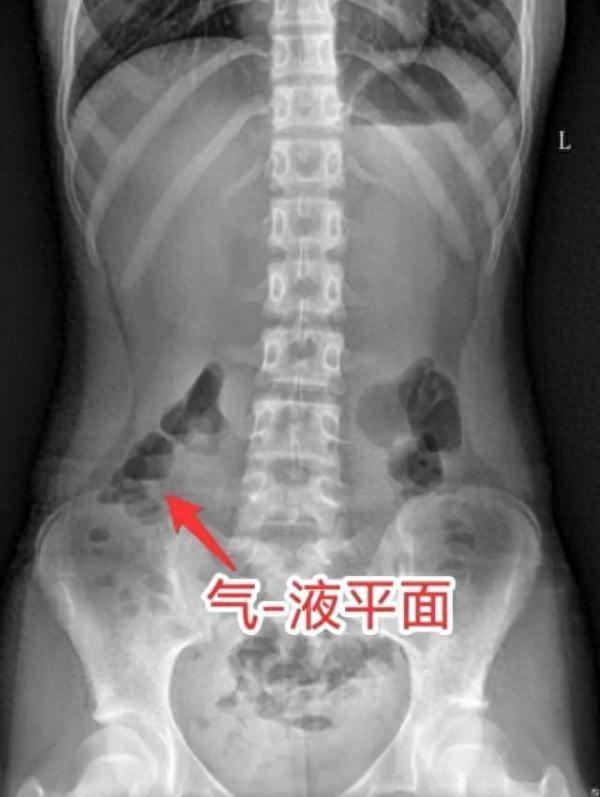

到医院后,根据小宁的症状及相关检查结果,被诊断为不完全性肠梗阻。医生给予开塞露灌肠通便,腹胀腹痛立马减轻,同时输液补钾纠正水电解质酸碱紊乱。

据该院急诊科副主任胡世华介绍,“痛、吐、胀、闭”是典型的肠梗阻症状。引起小宁肠梗阻的原因,主要是近期小宁暴饮暴食,胃肠消化能力达到上限,胃肠蠕动“罢工”,胃肠道内未完全消化的食物、积聚的气体和粪便不能顺利通过胃肠道,从而出现腹痛,停止排气排便。